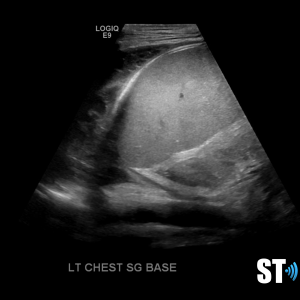

Pleural Effusion

Pleural effusion is a build up of fluid between the layers of the pleura. Scanning subcostally will show fluid above the diaphragm. Scanning intercostally will show fluid anterior the lung. Common causes for pleural effusion is infection, inflammation and malignancy.

The fluid can be anechoic or echogenic in cases of increased exudates, empyema, hemothorax and chylothorax (lymph collection). There may also be septations.